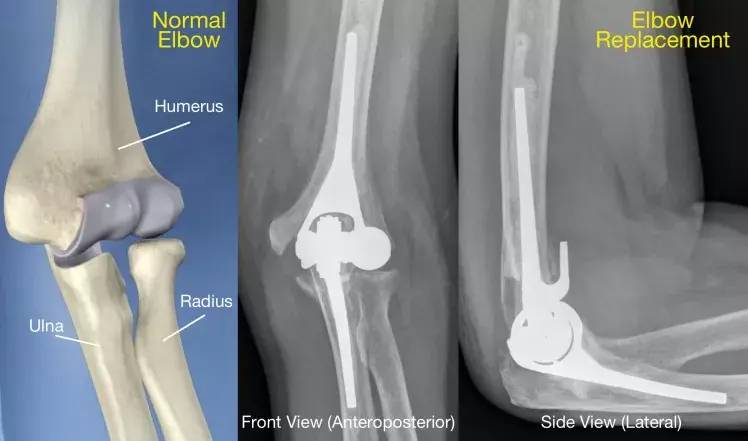

The elbow is a hinge joint which is made up of three bones:

- The humerus (upper arm bone)

- The ulna (forearm bone on the pinky finger side)

- The radius (forearm bone on the thumb side)

What is elbow replacement surgery ?

In total elbow replacement surgery, the damaged parts of the upper arm bone and the forearm bone are replaced with artificial components.

The artificial elbow joint is made up of a metal and plastic hinge with two metal stems. The stems fit inside the hollow part of the bone called the canal.